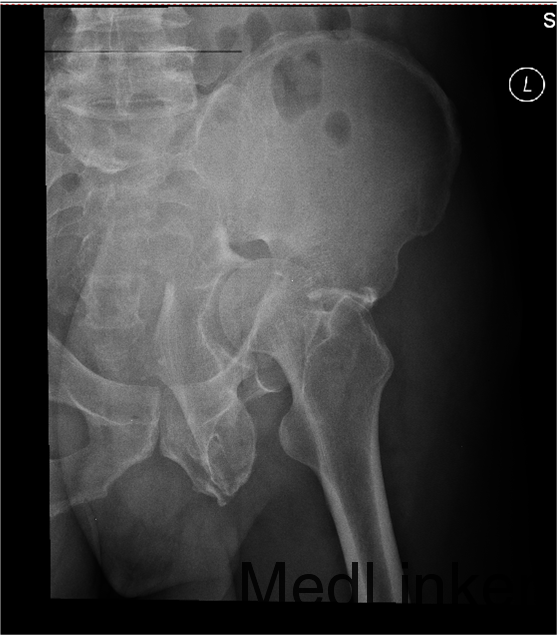

1.患者老年男性,以“车祸左髋部疼痛活动受限3天”为主诉入院。 2.现病史:患者自述于2014-11-04日晚下午7点发生机动车肇事,伤后患者急救车送往孤山二院,诊断为左髋臼骨折,当地医院未经任何治疗。急来中国医科大学附属盛京医院第五骨科创伤骨科治疗。我科以“左髋臼骨折”为主要诊断收入院。今来我院就诊,患者病来一般状态可,生命体征平稳,无发烧无发热,饮食睡眠可。

专科查体:患者平车入病房,左腿内收内旋屈曲畸形,左髋部压痛(+),叩击痛(+),骨盆分离试验阳性,活动受限,双下肢感觉未见异常,活动可,双侧足背动脉搏动可触及,双侧足趾活动灵活。